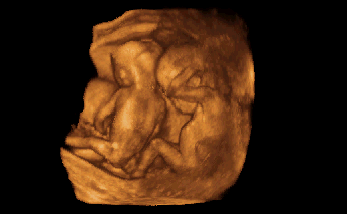

3-D / 4-D Ultraschall

Beeindruckend ist die dreidimensionale Darstellung in der Schwangerschaft, besonders wenn die Bewegungen des Babys zusätzlich "live" gesehen werden können (4-D). Dies gibt Ihnen als werdende Mutter einen ersten Blick auf ihr Kind und damit Sicherheit und Beruhigung.

Nebenan sehen Sie Beispiele für die dreidimensionale Darstellung